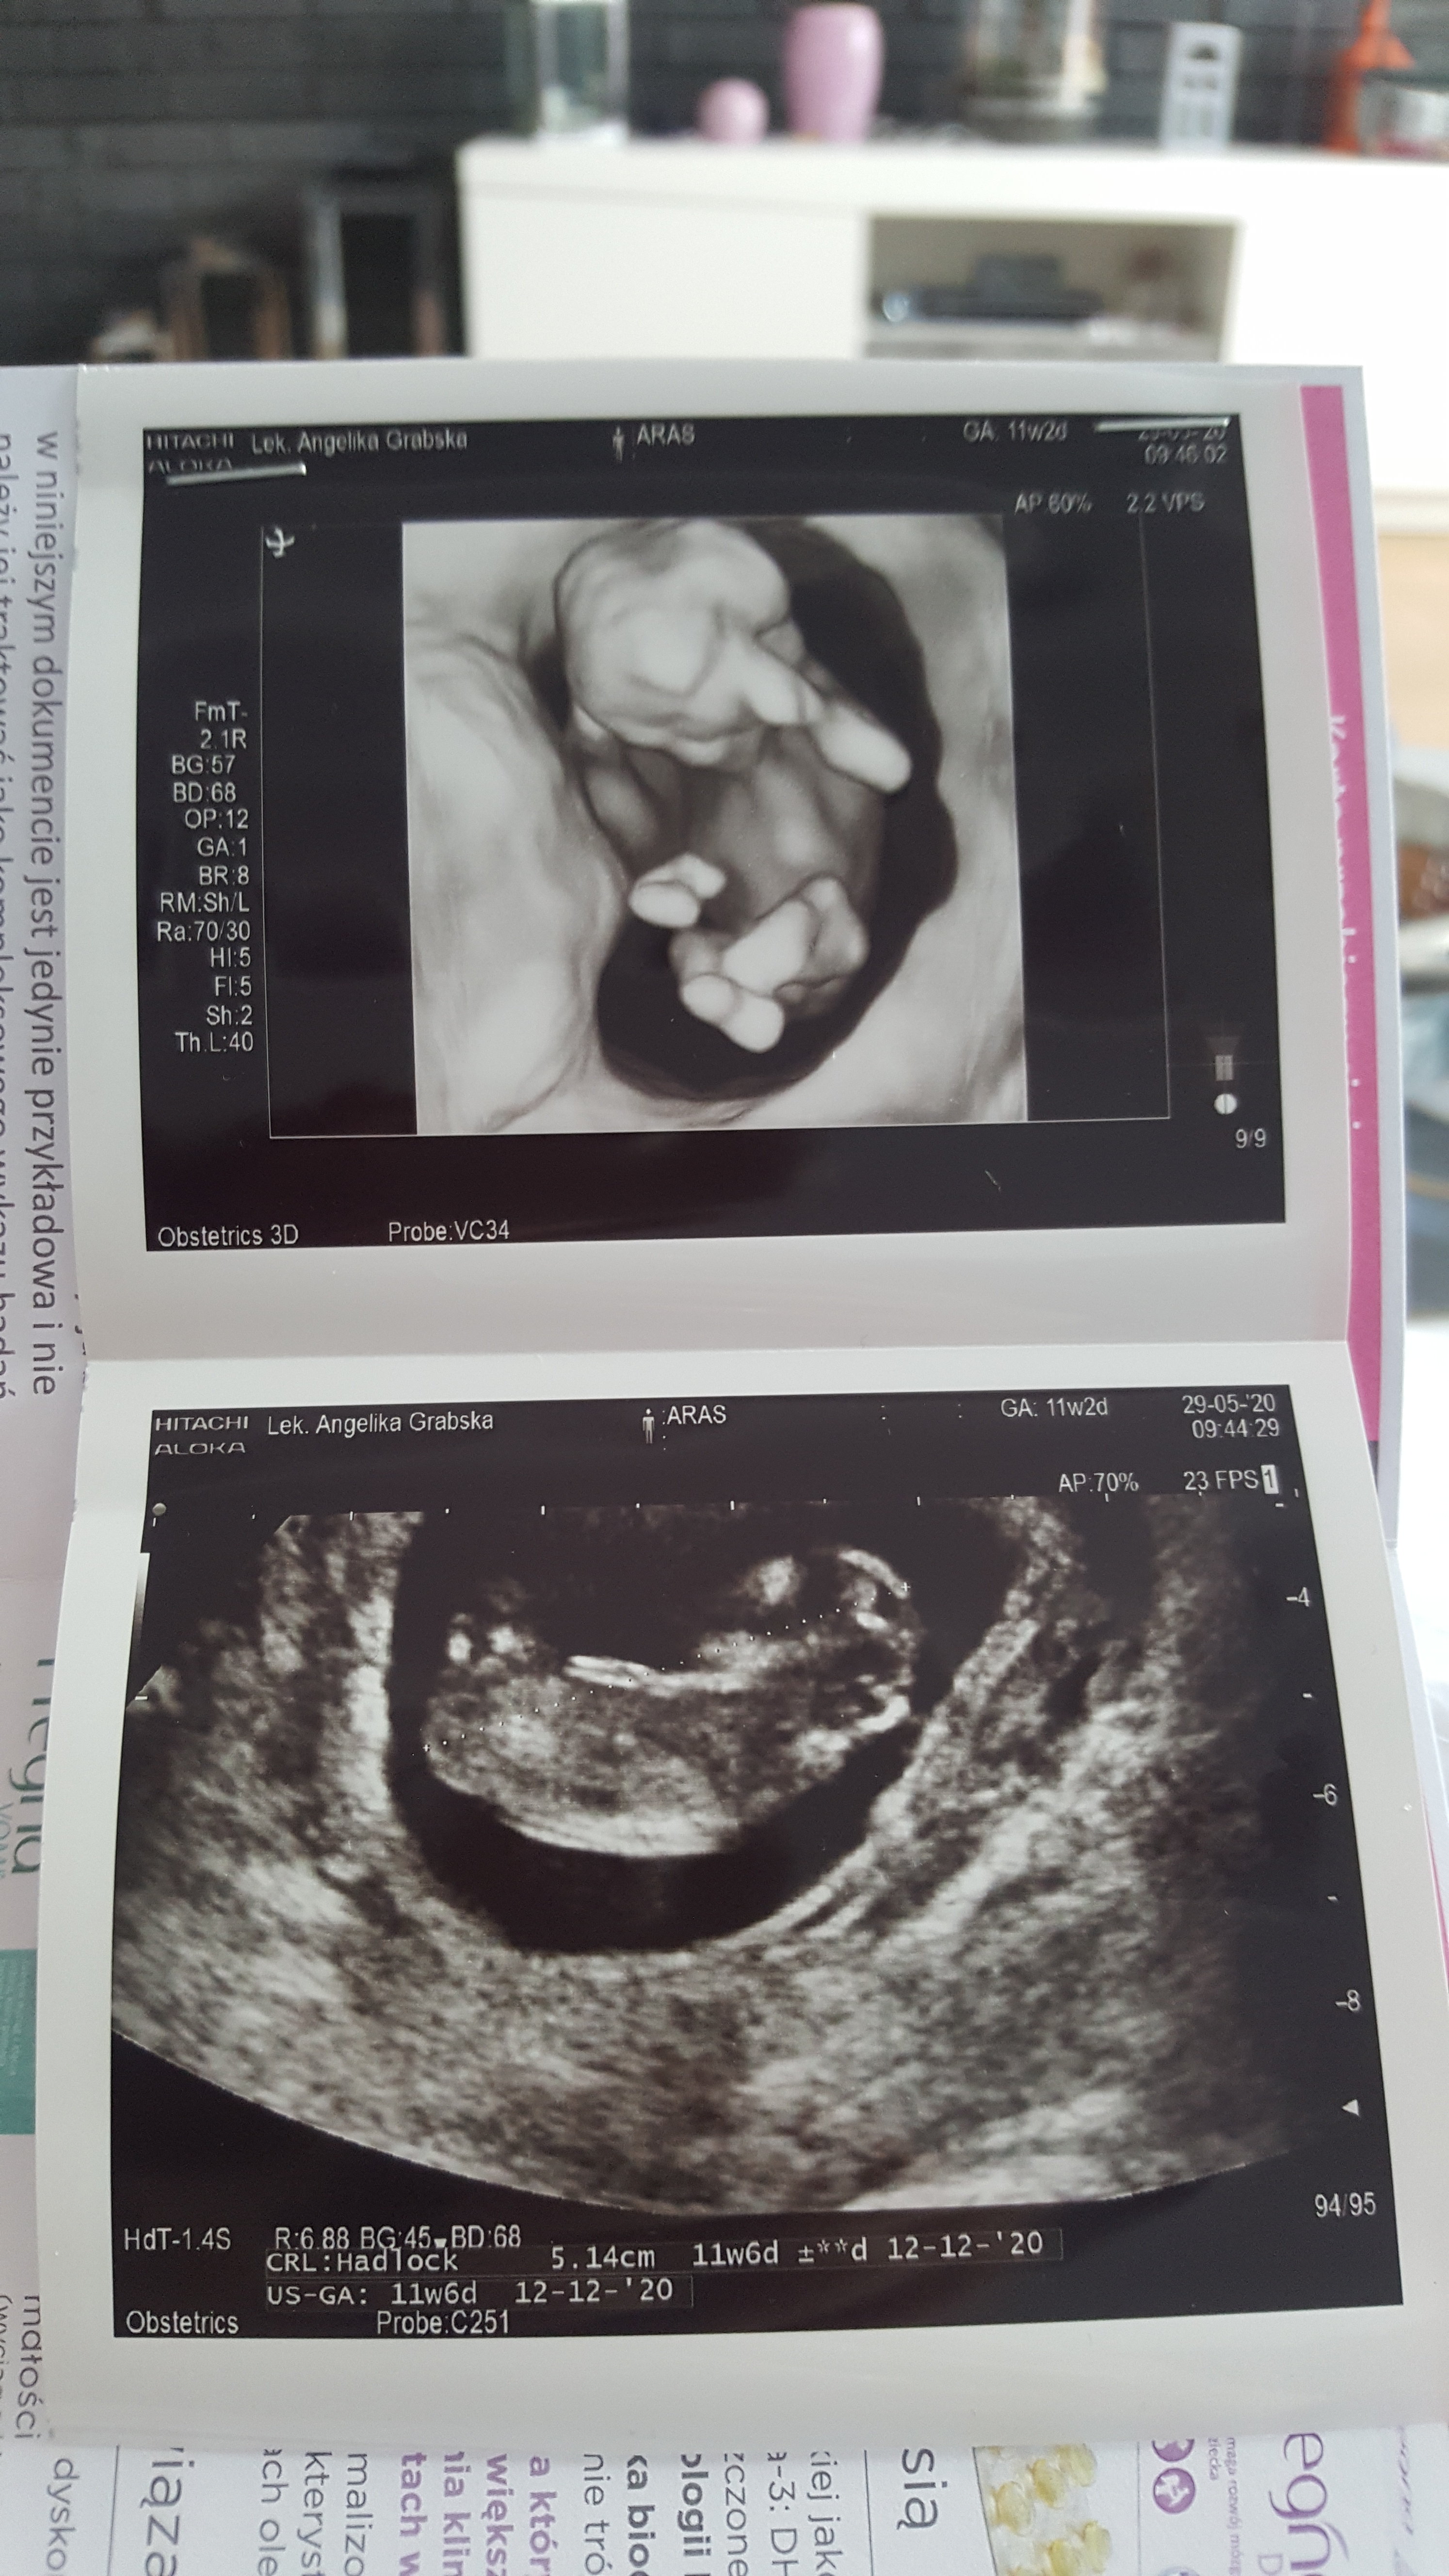

Dziewczyny zaraz będę nadrabiać, ja mam dziś 11+5 I termin na 12.12 więc będziemy rodzić liniowo ;p

Czekam na badanie krwi. Płyn markowy 1.7 wiec w normie, kość nosowa ok.

Bejbis ma 6.18cm

Z ust wychodzi 12t4d (Ja wlansie między 12t.3d A 12t4d mam w aplikacjach) termin na 7.12